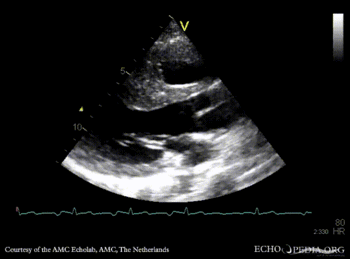

PSAX